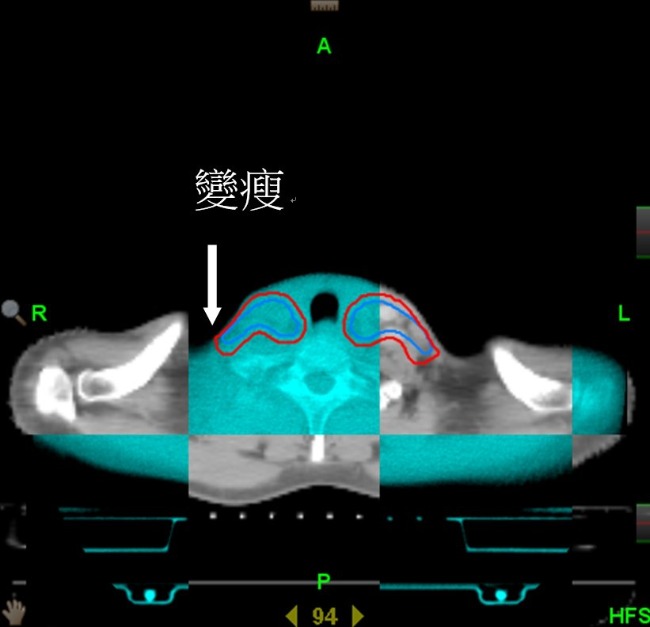

謝忱希 緊急召集亞東頭頸癌團隊替張先生治療,採用「高階螺旋刀影像導航系統配合階梯式加強技術」精準治療,除了能降低周圍器官損傷外,更能減少副作用。而張先生除了配合團隊使用手術切除口腔腫瘤並重建,術後再透過放射線合併化學治療,並果斷的戒除不好的習慣,五年後,健保卡上的重病註記終於消失,在醫病雙方努力結果下,戰勝口腔癌。

謝忱希 指出,頭頸部治療中,強度調控放射線治療(IMRT)是多數醫院所採用的治療技術,亞東醫院 同時擁有螺旋刀影像導航系統(HT)與強度調控放射線治療技術,相比傳統的治療方式,IMRT可提供更好的腫瘤治療與降低對重要器官的傷害。根據亞東醫院 長期追蹤數據顯示,螺旋刀比強度調控放射線治療能提供更好的腫瘤治療,以「螺旋刀配合階梯式加強技術」,可增加頭頸癌的控制率與降低局部復發率及副作用的嚴重度,螺旋刀可提供病人更好的腫瘤局部控制率,最終便可達到更好的長期存活機會。